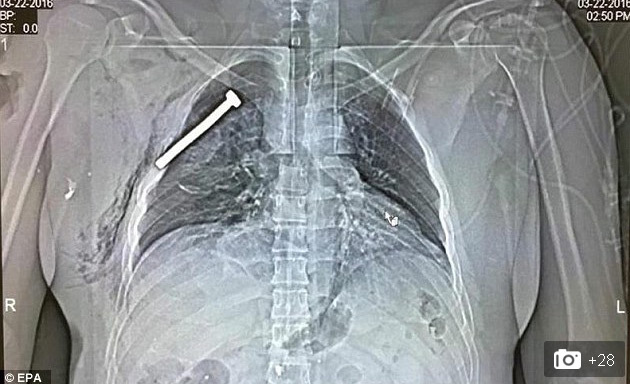

Loại bom khủng bố Brussels đáng sợ ra sao?

Những hình ảnh chụp X-quang vết thương của các nạn nhân cho thấy sự đáng sợ và máu lạnh của những kẻ tấn công.